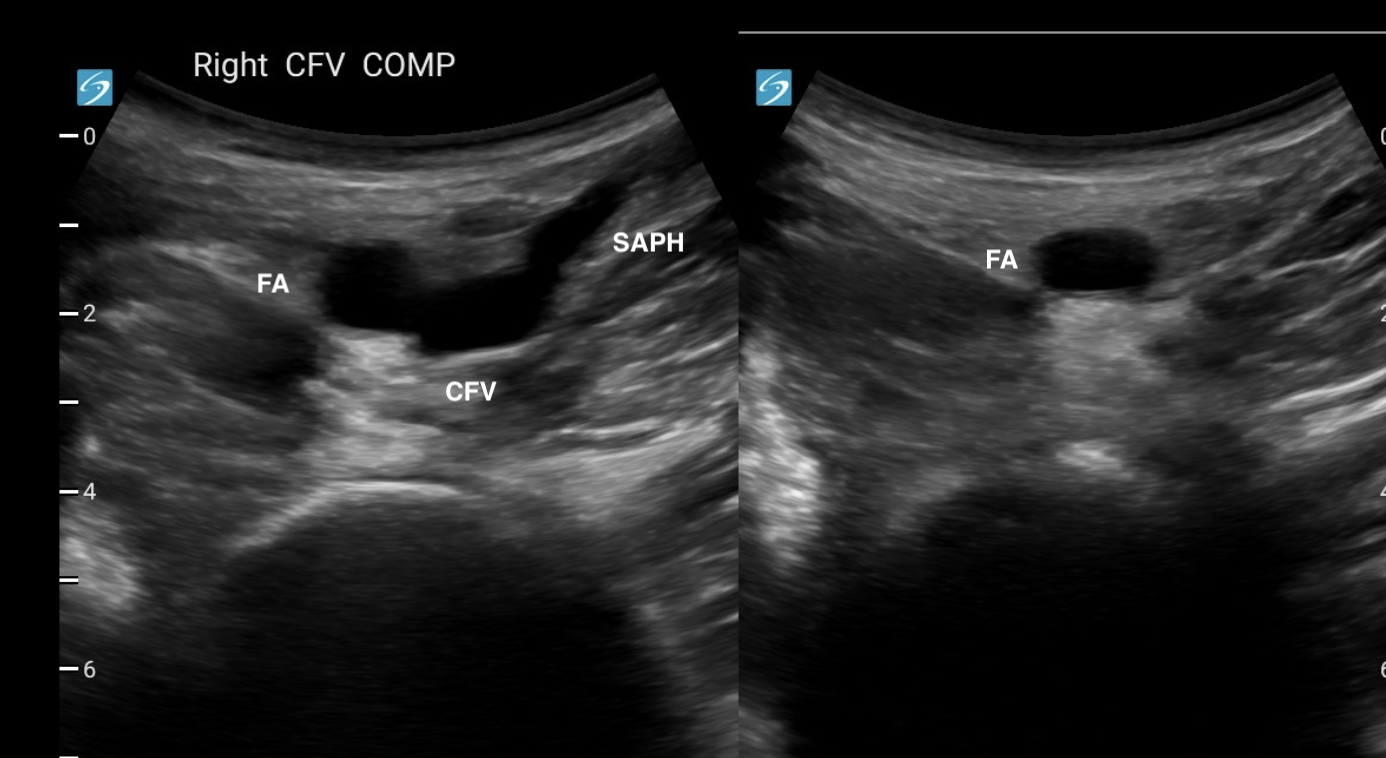

COMMON FEMORAL VEIN

Find the CFV in the inguinal region and image it at its origin. This is where the long saphenous vein joins it medially.

Compress the vein against the femur by putting downward pressure on the probe while keeping the vein in view. It's easy to lose sight of the vein by accidentally fanning cranially or caudally when you do this. That's why it's important to stabilise your palm/wrist on the patient's leg.

A normal vein will compress so that the lumen completely disappears.

The image on the right only shows the FA, because the CFV and saphenous vein have been compressed.